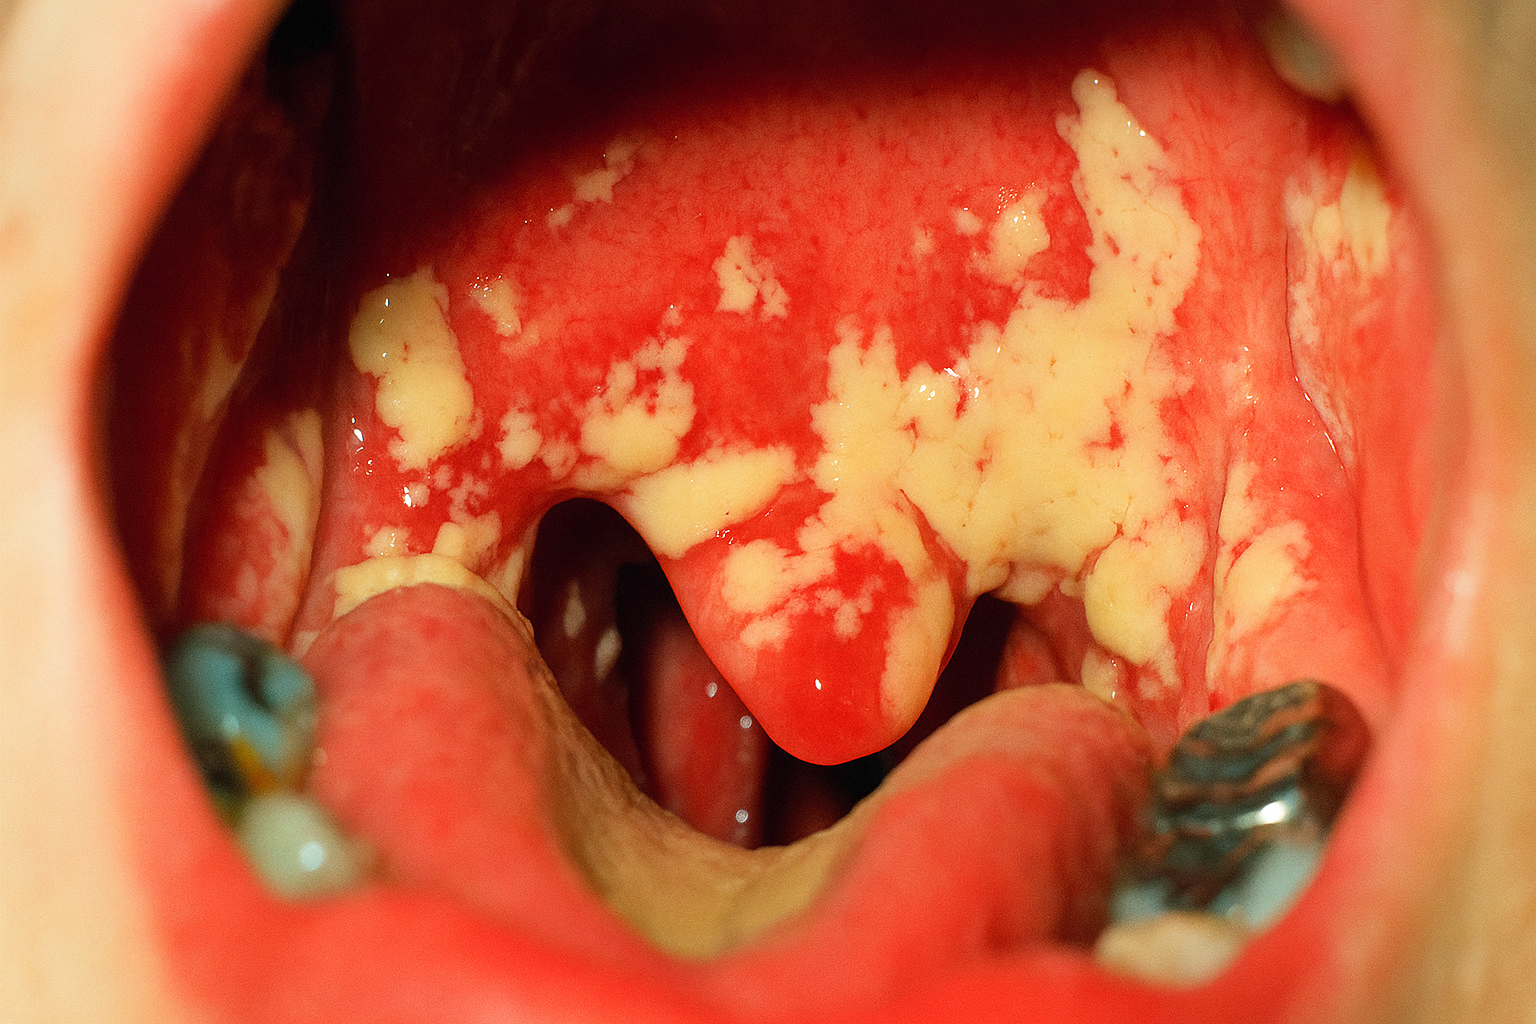

La causa fúngica más común de la lengua blanca es la candidiasis oral, también conocida como muguet. Esta es una infección oportunista causada por el crecimiento excesivo de la levadura Candida albicans, un hongo que vive de forma natural en nuestra boca sin causar problemas. Sin embargo, cuando el equilibrio del microbioma oral se altera, la Candida puede multiplicarse sin control. Afortunadamente, identificarla es relativamente sencillo por sus características clínicas.

La candidiasis oral se presenta con signos muy distintivos. El más evidente son las placas o parches de color blanco cremoso, a menudo descritos con una apariencia similar al “requesón” o “leche cortada”. Estas lesiones no solo aparecen en la lengua, sino que también pueden extenderse al interior de las mejillas, el paladar y la garganta. A diferencia de otras causas de la lengua blanca, estas placas se pueden raspar. Al hacerlo, se revela una base roja, inflamada y que puede sangrar ligeramente. Otros síntomas que pueden acompañar a esta condición incluyen:

- Sensación de ardor o dolor en la boca.

- Una sensación algodonosa en la boca.

- Pérdida del gusto o un sabor desagradable y metálico.

- Enrojecimiento y grietas en las comisuras de los labios (queilitis angular).